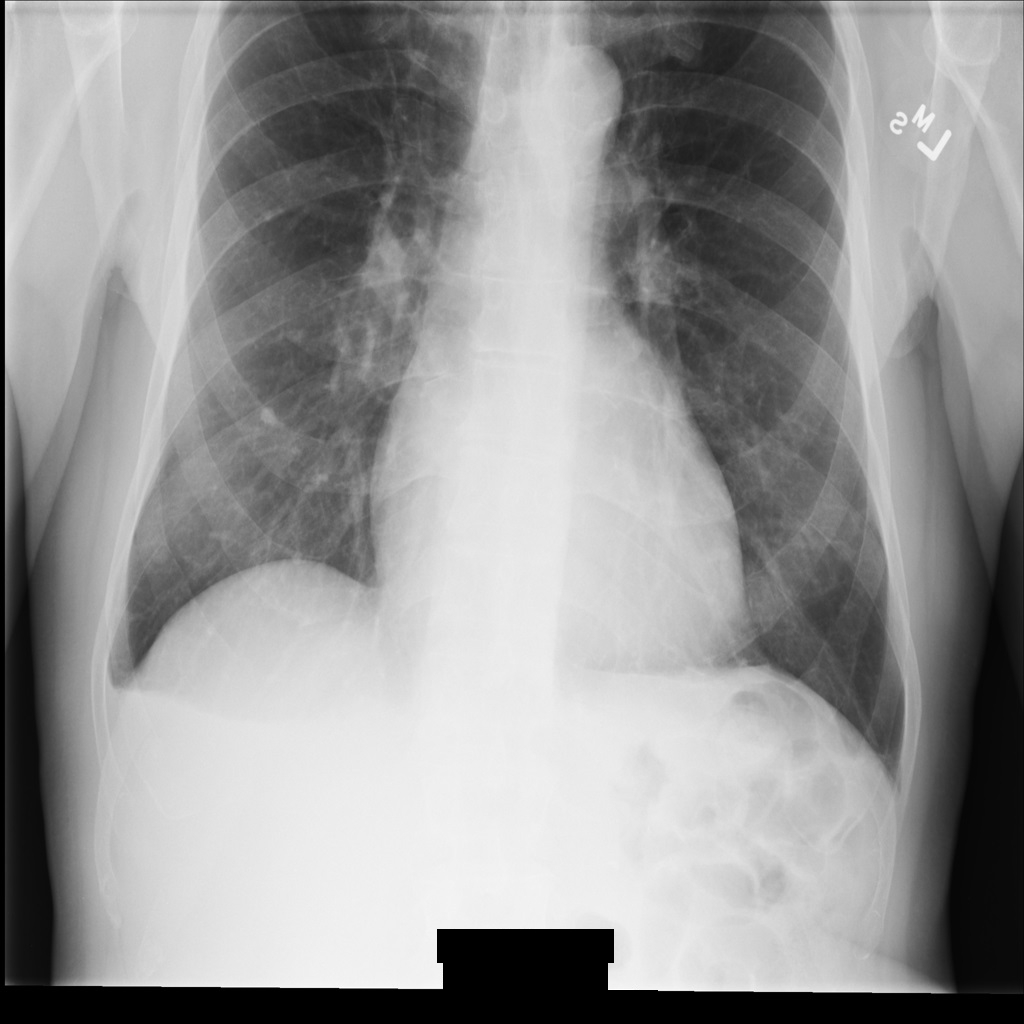

Imagen de muestra

Algunas muestras de esta página contienen el resultado de la imagen anonimizada. En cada ejemplo se usa la siguiente imagen original como entrada. Puedes comparar la imagen de salida de cada operación de anonimización con esta imagen original para ver los efectos de la operación:

Después de desidentificar la imagen con REDACT_ALL_TEXT, la imagen tiene este aspecto. Fíjate en que se ha ocultado todo el texto superpuesto en la parte inferior de la imagen.

Después de desidentificar la imagen con REDACT_SENSITIVE_TEXT_CLEAN_DESCRIPTORS, la imagen tiene este aspecto. Ten en cuenta que no se ha ocultado todo el texto superpuesto en la parte inferior de la imagen. El texto Female sigue mostrándose porque PatientSex (0010,0040) no es uno de los infoTipos DICOM predeterminados.